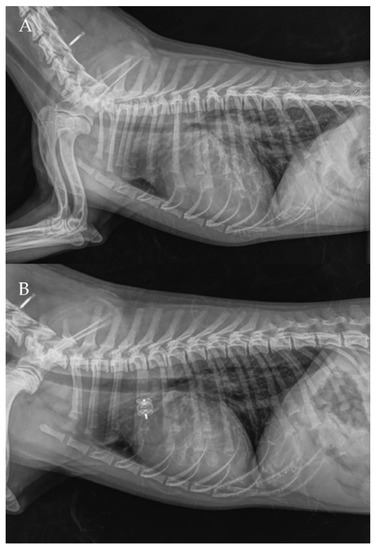

Figure 8. Pre-procedure (A,B) and post-procedure (C,D) left lateral and dorso-ventral thoracic radiographs of Case 1. L: left; R: right.

The thoracic radiographs performed before and just after the procedure showed a reduction in the cardiac silhouette as well as significant reduction of the over-circulation vascular pattern for all dogs (Figure 8, Figure 9, Figure 10, Figure 11 and Figure 12).